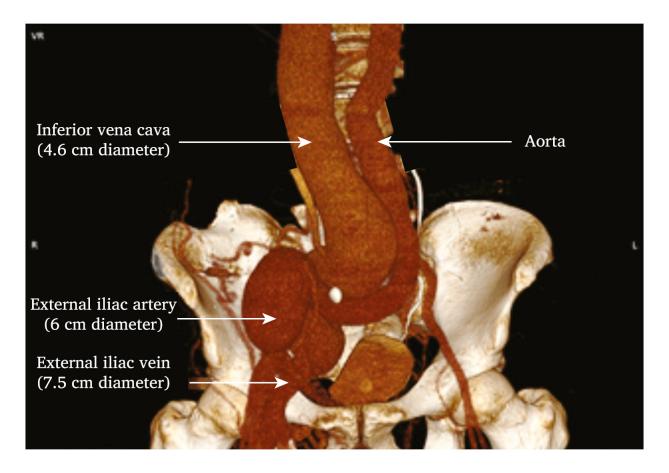

A 40 year old man with past history of gunshot wound of the right flank complained of severe right limb swelling and shortness of breath. An AVF between the right external iliac artery and external iliac vein responsible for the cardiac failure was diagnosed. A 40 year old woman with past history of spinal surgery complained of breathlessness and lower limb oedema. She presented with recurrent episodes of ascites and dyspnoea. An AVF between the right common iliac artery and the common iliac vein responsible for high output cardiac failure was diagnosed. Open surgery was performed in both patients and treatment of the AVFs led to the resolution of all symptoms. Follow up at four and three years, respectively, was uneventful in both cases.

一名40岁男性,既往有右侧腰部枪伤史,主诉右下肢严重肿胀和呼吸急促。诊断为右髂外动脉与髂外静脉之间的AVF导致心力衰竭。一名40岁女性,既往有脊柱手术史,主诉呼吸急促和下肢水肿。她反复出现腹水和呼吸困难。诊断为右髂总动脉与髂总静脉之间的AVF导致高输出量心力衰竭。两名患者均接受了开放手术,AVF的治疗使所有症状得到缓解。分别在术后四年和三年进行随访,两例均无异常。